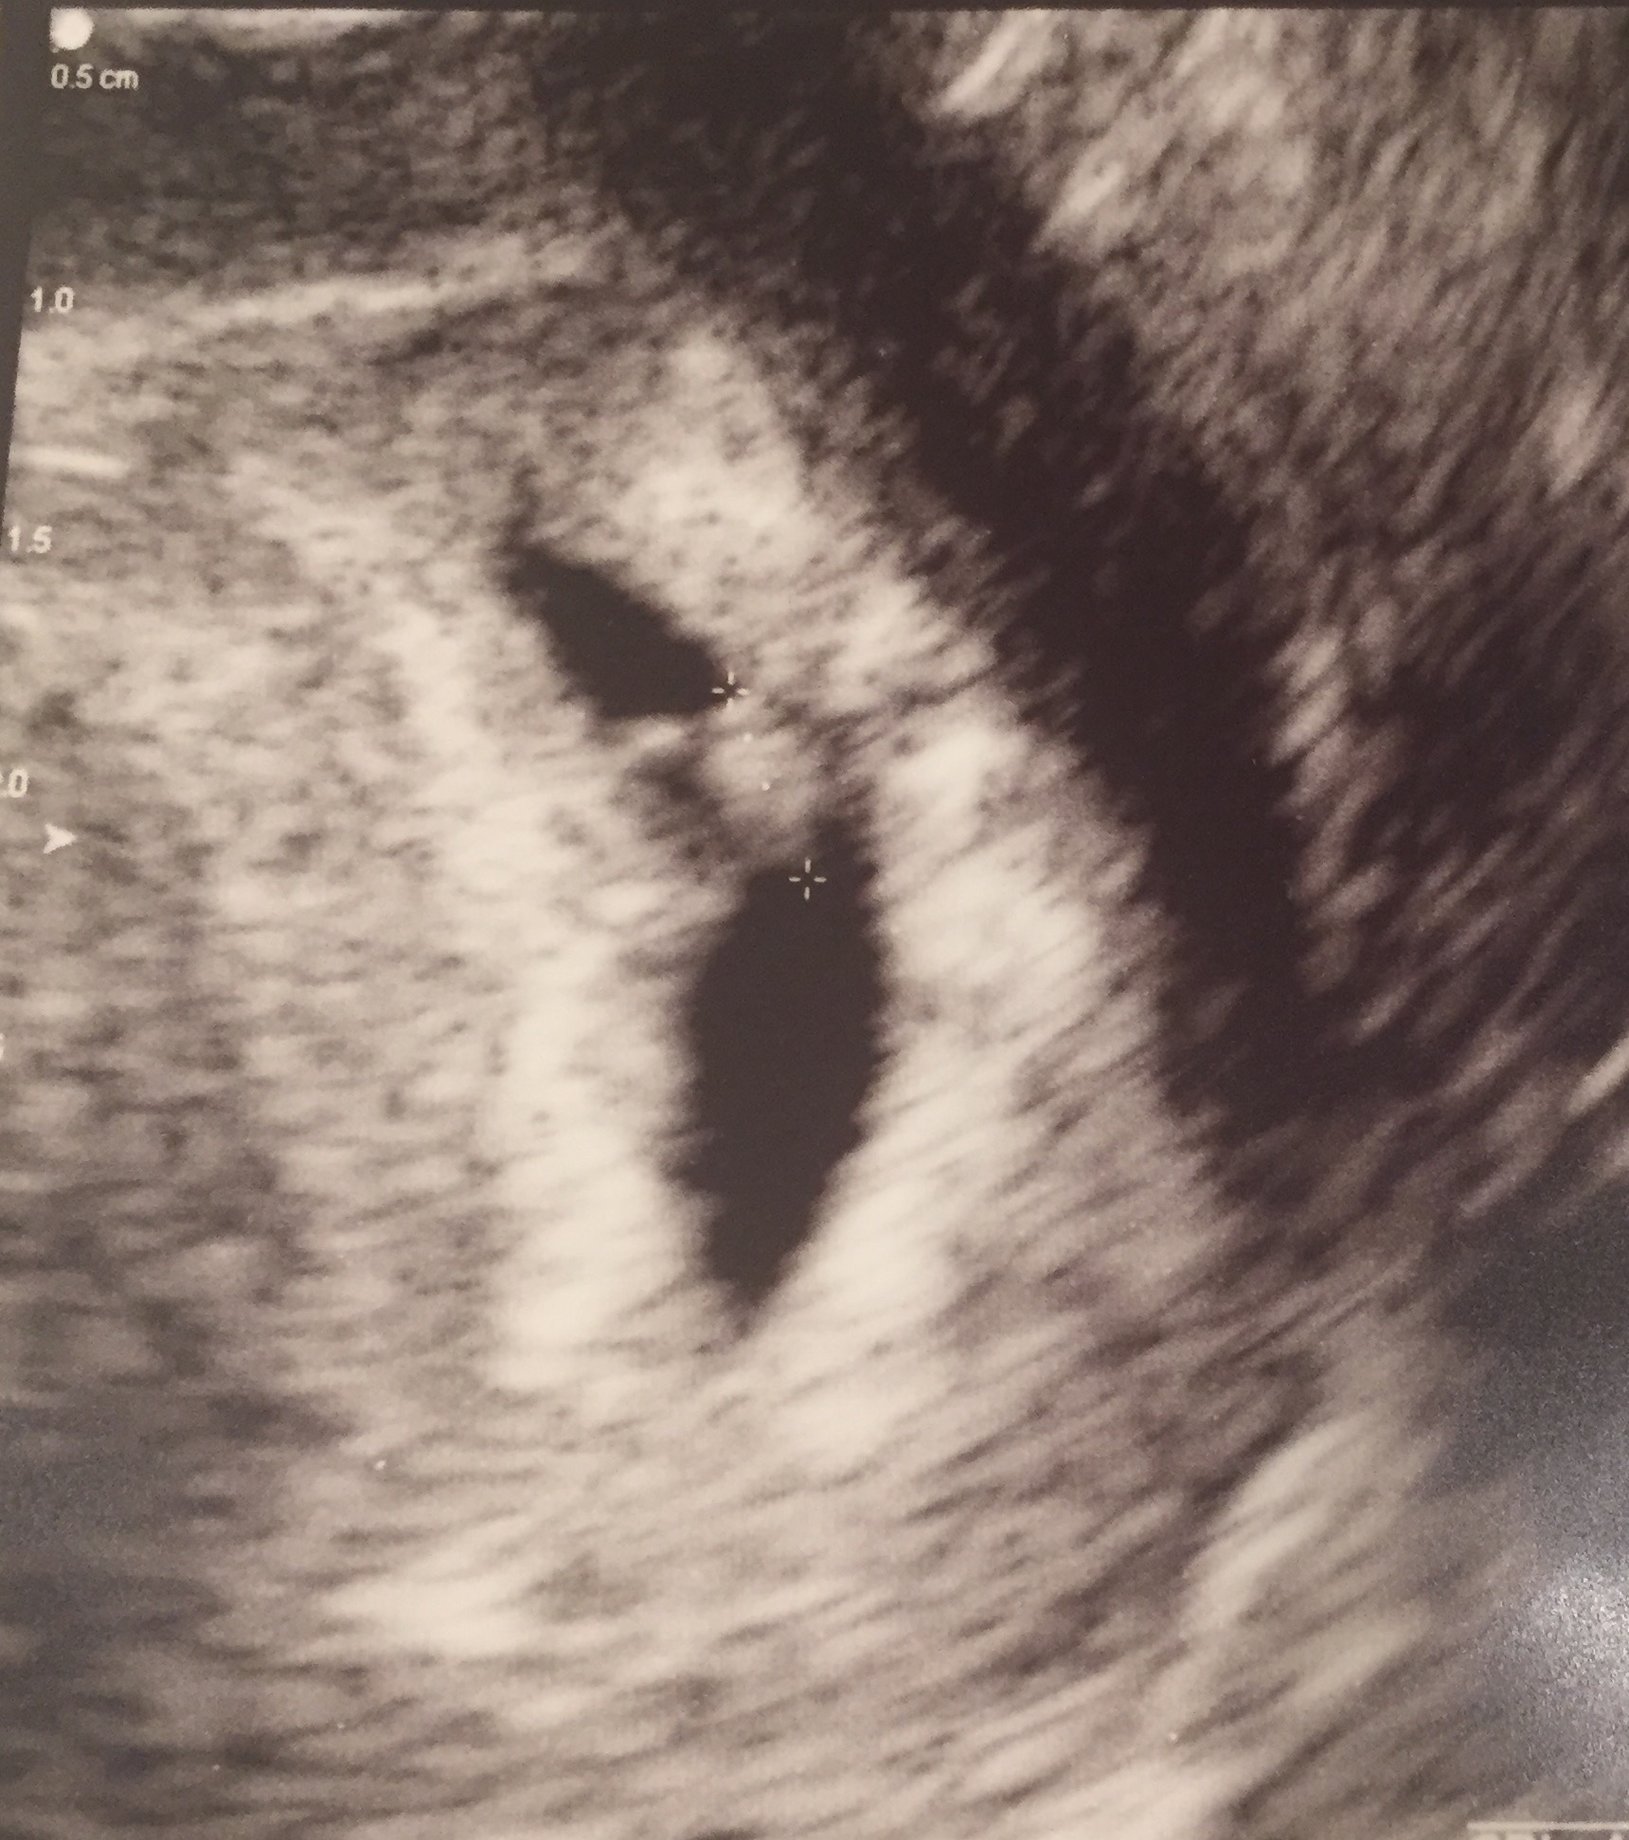

Going for my second ultrasound this Friday and so nervous. Hoping to see some progress.

Glad you started this thread. Im super excited and nervous all in one. We did one iui, two rounds of IVF. Three FET's within the two rounds of IVF. We did PGS testing/ ICSI with all the embryos. 1st time we transferred one, two the second time and this last time one boy embaby. Here I am at 5 weeks 2 days pregnant. They are guessing my due date is January 10th. I go for my first ultrasound tomorrow morning. Excited to continue chatting with you ladies. You've been a tremendous support!!

I get to go for another ultrasound this Wednesday. I'll be almost 7 weeks by then.